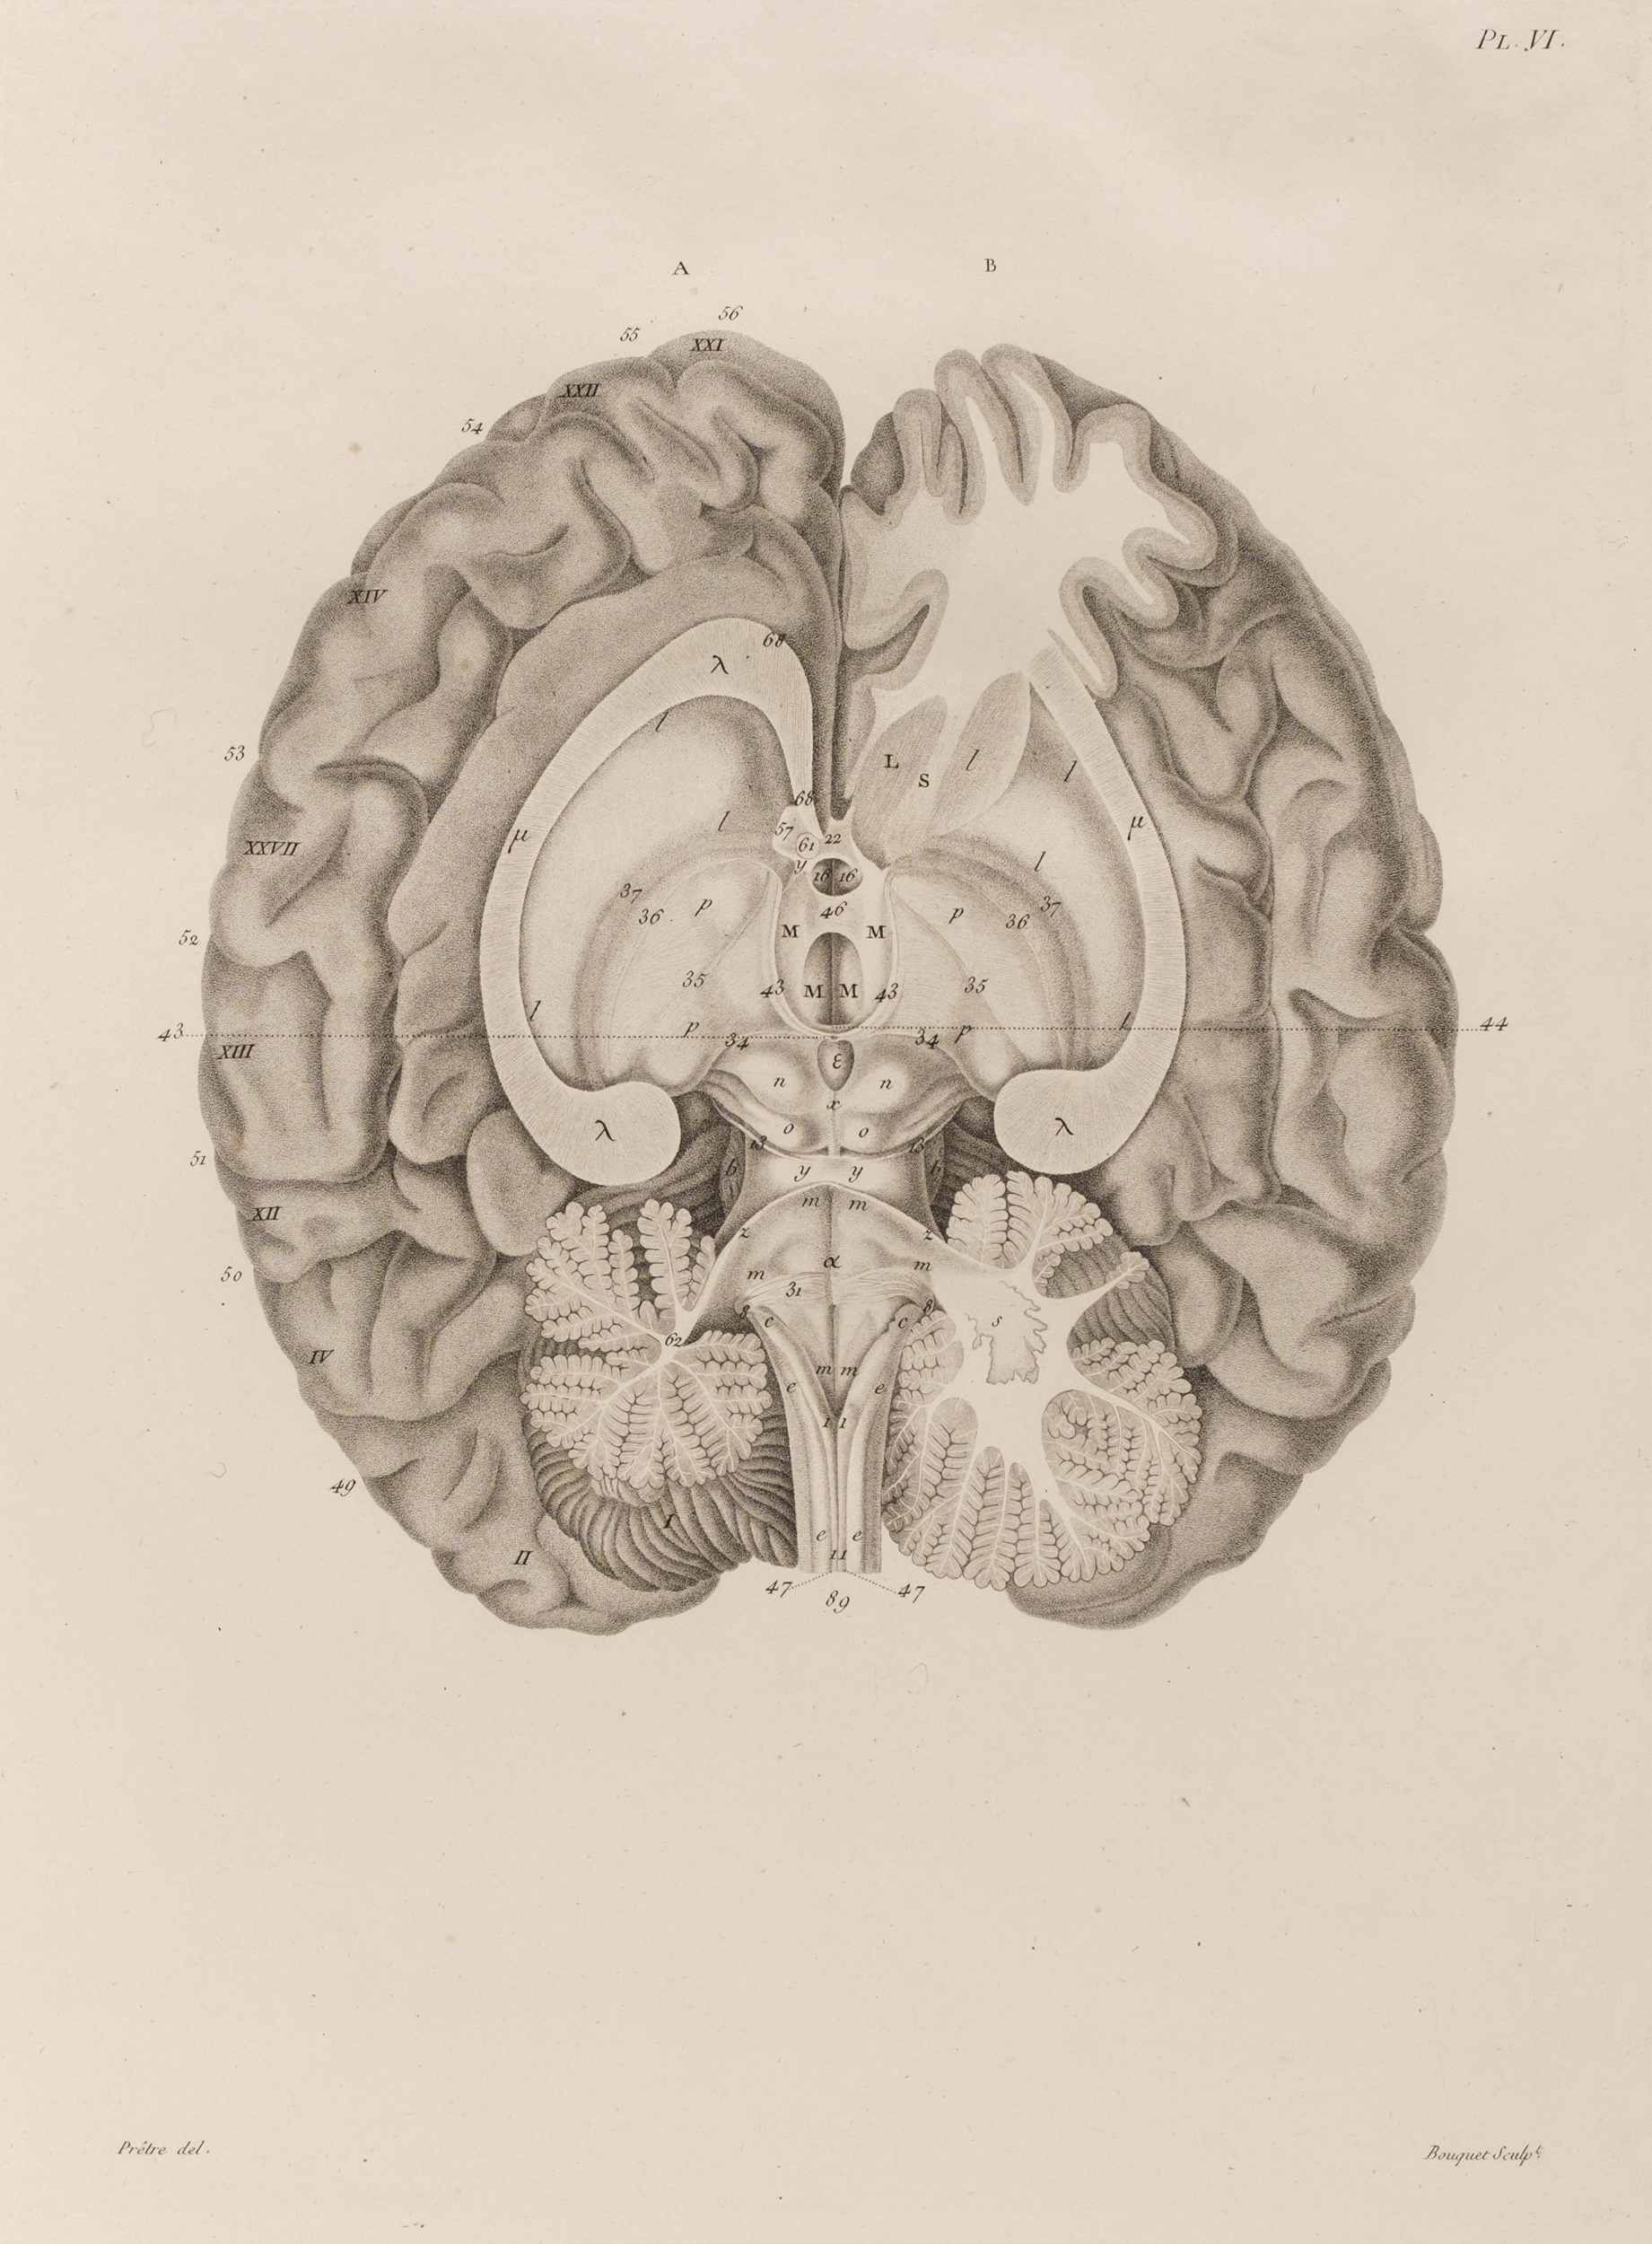

Caldwell (Charles). Elements of Phrenology, (Second Edition, Greatly Enlarged), with a Preliminary Discourse in Vindication of the Science, Against an Attack on it by Francis Jeffrey... , printed by A. G. Meriwether, Lexington, Kentucky, 1827, engraved frontispiece, some indistinct pencil notes and underscoring throughout, heavily browned, author's presentation inscription to James De Ville to front free endpaper, dated 25 June 1841, later ownership signature of E. Basil Wedmore (1898) to following endpaper, original linen-backed boards, soiled and worn, 8vo, together with: Mackenzie (George Steuart , Illustrations of Phrenology, Edinburgh: Archibald Constable & Co., 1820, engraved portrait frontispiece and 17 plates, publisher's adverts at rear, inner hinges broken and preliminary leaves unstitched, browned throughout, untrimmed, contemporary boards with crude linen reback, soiled and worn, 8vo, plus Struve (Gustav von), Handbuch der Phrenologie, Leipzig: F. A. Brockhaus, 1845, half-title, 6 lithographic plates and illustrations to text, heavy spotting or browning throughout, uncut, original printed wrappers, a little rubbed and soiled, 8vo, plus others related on 19th-century phrenology practitioners and the debates, including some pamphlets and extracts and 4 volumes of Edinburgh Review, plus 10 modern reference works (Quantity: 38)

Caldwell (Charles). Elements of Phrenology, (Second Edition, Greatly Enlarged), with a Preliminary Discourse in Vindication of the Science, Against an Attack on it by Francis Jeffrey... , printed by A. G. Meriwether, Lexington, Kentucky, 1827, engraved frontispiece, some indistinct pencil notes and underscoring throughout, heavily browned, author's presentation inscription to James De Ville to front free endpaper, dated 25 June 1841, later ownership signature of E. Basil Wedmore (1898) to following endpaper, original linen-backed boards, soiled and worn, 8vo, together with: Mackenzie (George Steuart , Illustrations of Phrenology, Edinburgh: Archibald Constable & Co., 1820, engraved portrait frontispiece and 17 plates, publisher's adverts at rear, inner hinges broken and preliminary leaves unstitched, browned throughout, untrimmed, contemporary boards with crude linen reback, soiled and worn, 8vo, plus Struve (Gustav von), Handbuch der Phrenologie, Leipzig: F. A. Brockhaus, 1845, half-title, 6 lithographic plates and illustrations to text, heavy spotting or browning throughout, uncut, original printed wrappers, a little rubbed and soiled, 8vo, plus others related on 19th-century phrenology practitioners and the debates, including some pamphlets and extracts and 4 volumes of Edinburgh Review, plus 10 modern reference works (Quantity: 38)